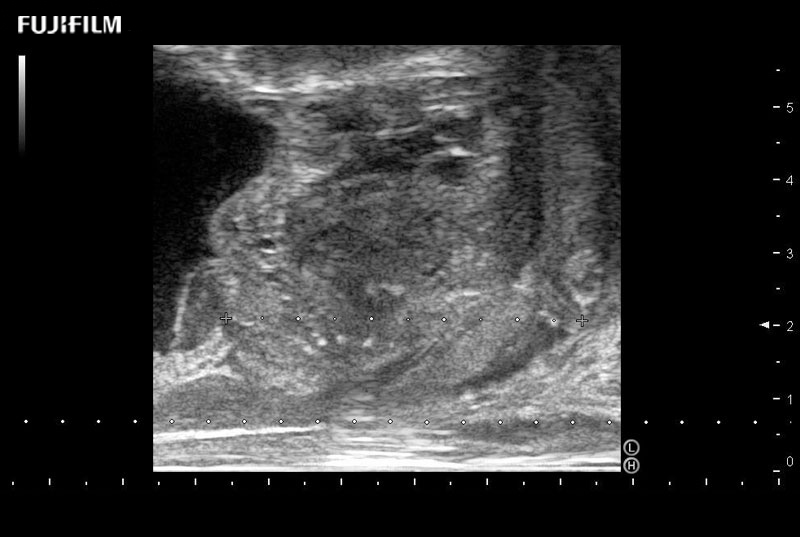

including: B-Mode, Color Doppler, Power Doppler, Fine Flow

– better visualization of tumors to improve understanding of blood flow information

38mm footprint is ideal for scrotal and penile doppler imaging

Main Specifications:

Larger footprint is ideal for scrotal and penile doppler imaging

Designed for high-resolution imaging of the scrotal and penile regions. This advanced transducer offers exceptional image quality, user-friendly features, and specialized functionalities to support accurate urological diagnostics and enhance patient care.